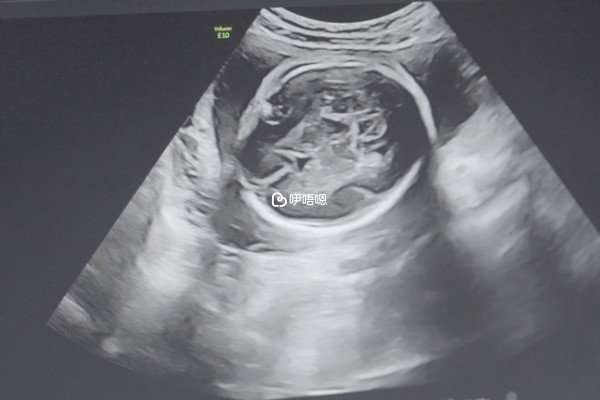

nt彩超單子上的nub點一般在胎兒雙腿間接近屁股的位置,但一般是無法準確判斷男女性別的,如果當nt報告上類似有小尾巴的東西凸出,這裡就是大家所說的nub點,也就是平時說的胎兒生殖結節,之所以部分人說nt單上出現有nub點則代表懷的就是男孩,是因為這個點看起來有點像男孩的生殖器官,但其實這個也不是絕對的,因為不管是男孩還是女孩這個位置都會有個小尾巴,所以通過nut點來判斷胎兒性別是不準確的。

nt檢查主要是判斷胎兒是否存在染色體或者是身體畸形的一個重要指標,如果nt檢查結果在正常的範圍值內,那麼代表胎兒生長髮育正常,若超過了範圍值,那麼就需要做進一步的檢查,而部分人也會通過nt檢查和nub來判斷胎兒性別,主要有以下幾點: